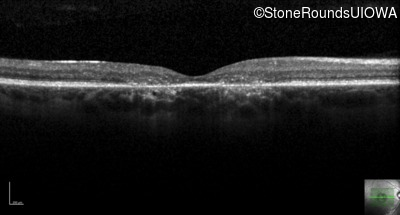

XL Cone and Cone Rod Dystrophy (IA1bi)

Age at visit: 28 years

This 28 year old man has recently noticed some difficulty with fine visual tasks such as tying a fishing lure to a fishing line.

Diagnosis & molecular findings

Disease Gene Allele 1 variant(s) Allele 2 variant(s) Inheritance mode

XL Cone and Cone Rod Dystrophy RPGR Glu1031 del1gA   XL